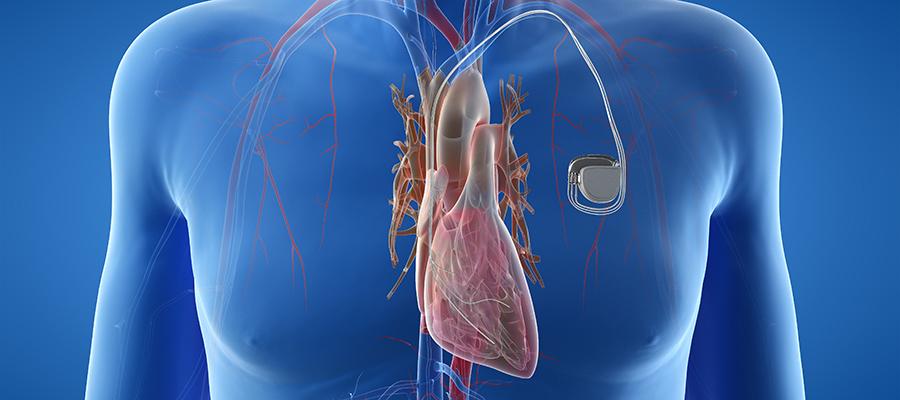

The cardiac restoration systems market is witnessing robust dynamism driven by technological innovation and increasing clinical adoption, setting a promising trajectory for sustained business growth. Industry players are leveraging advanced regenerative therapies and minimally invasive techniques, expanding the market scope amid rising cardiovascular disease prevalence globally. This evolving...